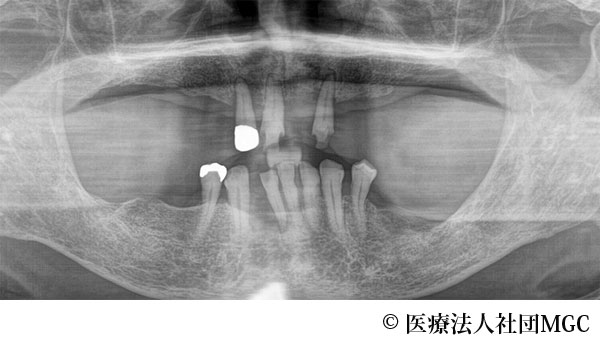

【症例1】上下All-on-4(オールオンフォー)

- 治療前

- 治療名

- 上下All-on-4(オールオンフォー)

- 費用

- 5,915,800円(税込)

- 期間

- 8ヵ月

患者様の症状

歯がボロボロで食事が困難であるとご来院されました。

治療法

ご相談の結果、患者様の生活の質(QOL)を向上させ、しっかり噛めるように上下All-on-4(オールオンフォー)を行いました。

治療結果

機能性、審美性ともに改善し、満足していただけました。

※治療結果は患者様によって個人差があります。

治療を行う上での注意点(リスク・副作用)

インプラント周囲炎の可能性、まれに歯が欠ける可能性があります。